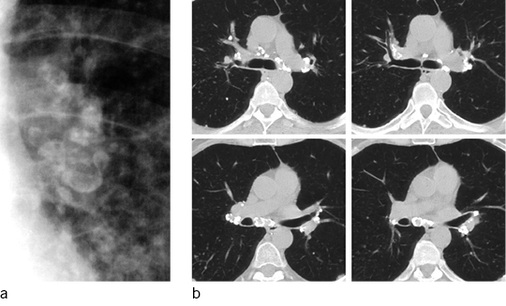

Nachdem durch arbeitshygienische Maßnahmen die komplizierten verschwielenden Verlaufsformen der Silikose nahezu völlig zurückgedrängt wurden, steht heute die chronische obstruktive Emphysembronchitis mit ihren schweren Folgen für die kardiorespiratorische Funktion im Vordergrund. Bereits 1972 wurde durch Otto u. von Hinüber beschrieben, dass die verschiedenen Formen des Emphysems unabhängig von lokalen Staubablagerungen und silikotischen Knötchen bei Autopsien beruflich staubbelasteter Personen deutlich häufiger als bei Autopsien nicht staubbelasteter Personen auftreten. Es finden sich fokale und generalisierte Emphysemformen wie das perinodöse Traktionsemphysem, das dilatative zentrilobuläre Emphysem bis hin zur generalisierten Form der sog. „schwarzen Löcherlunge“ sowie das bullöse bronchostenotische Emphysem, häufig mit einer persistierenden Bronchitis und Bronchiolitis kombiniert. Bei ausgeprägtem Lungenemphysem können anhand der Übersichtsaufnahme silikotische Noduli vollständig entgehen. Computertomographisch zeigen sich in diesen Fällen häufig neben dem ausgeprägten Emphysem zusätzlich Bronchialwandverdickungen als Zeichen einer Bronchitis sowie unscharfen zentrilobulären Knötchen als Zeichen einer Bronchiolitis und scharf berandete Noduli im Sinne silikotischer Knötchen (  Abb. 7 ). Das Ausmaß des Lungenemphysems korreliert nach Literaturangaben wohl deutlich mit der Einschränkung der Lungenfunktion, eine gute Korrelation mit der Ausprägung der nodulären Veränderungen besteht jedoch nicht (Bergin et al. 1986; Gevenois et al. 1998; Lopes et al. 2008; Meijer et al. 2011).